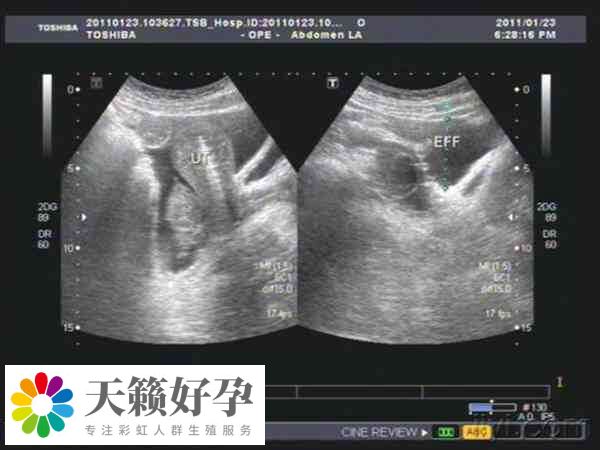

很多做試管嬰兒(er) 的姐妹為(wei) 了獲得更多卵子,會(hui) 在試管嬰兒(er) 前期投入大量的時間和精力,有甚者更是提出了增大促排卵藥量的方法,但盲目追求取卵數量是不科學的,比如有的患者直接促排26個(ge) 卵泡,至於(yu) 患者促排28個(ge) 卵泡做試管成功率高不高,還要從(cong) 以下幾個(ge) 方麵判斷。

患者促排28個(ge) 卵泡做試管時,如果質量不佳,或者培育出的胚胎質量差,都可能導致試管失敗。反之如果促排的28個(ge) 卵泡質量比較好,那麽(me) 培養(yang) 的胚胎質量也比較好,這時移植成功率也就相對較高。